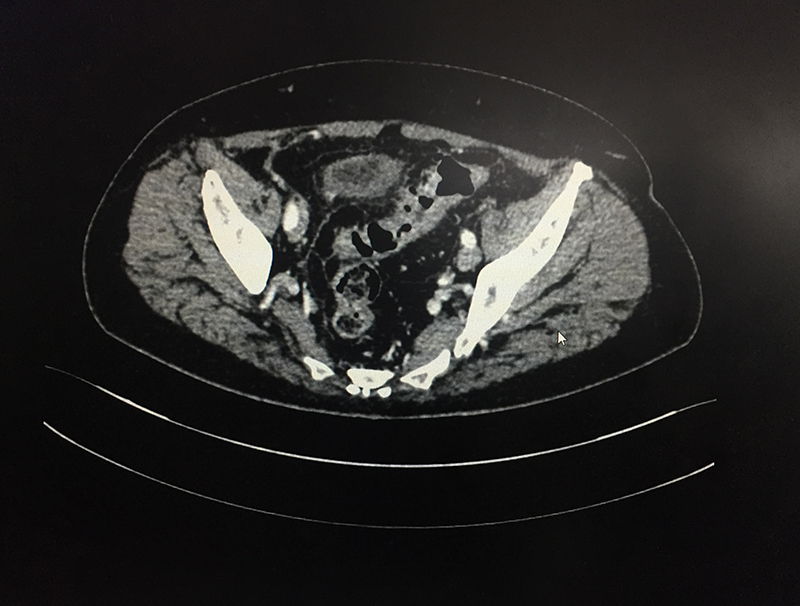

60 year old lady with an episode of sigmoid diverticular perforation with was managed with antibiotics and other supportive measures. A surgery was avoided at this time. She settled well, however started experiencing recurrent incapacitating abdominal pain due to sigmoid diverticular disease. A laparoscopic sigmoid colectomy and colorectal anastomosis was electively performed. She was discharged on postoperative day 5. She is now completely pain and symptom free.

When a patient with acute abdominal pain is diagnosed (clinical suspicion) with a possible diverticulitis, he/she needs further investigations; blood & imaging study (CT scan of abdomen & pelvis) to confirm the diagnosis, rule out complications and plan the treatment based on the laid out guidelines. Most patients without complications & few with complications like contained perforation abscess are managed with antibiotics and occasionally with percutaneous drainage. Few patient require a laparoscopic lavage and drainage. Those with major perforation and fecal contamination require emergency surgery. It is done as an open procedure or by laparoscopic route depending on available expertise & patient condition. The involved sigmoid colon is resected and an end colostomy (bringing out the proximal end) is performed. The colon is reconstructed at a later date once patient has fully settled. If patient is too sick to tolerate a major surgery only a diverting colostomy (to bring the intestine lumen out on surface) is performed.